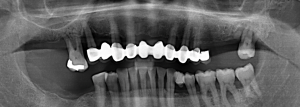

Pre-operative smile and orthopanthomogram. Fig. 1 (i, ii)